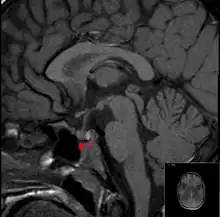

It is recommended that magnetic resonance imaging (MRI) scan of the pituitary gland is performed if the diagnosis is suspected; this has a sensitivity of over 90% for detecting pituitary apoplexy; it may demonstrate infarction (tissue damage due to a decreased blood supply) or hemorrhage.[1] Different MRI sequences can be used to establish when the apoplexy occurred, and the predominant form of damage (hemorrhage or infarction).[2] If MRI is not suitable (e.g. due to claustrophobia or the presence of metal-containing implants), a computed tomography (CT) scan may demonstrate abnormalities in the pituitary gland, although it is less reliable.[1] Many pituitary tumors (25%) are found to have areas of hemorrhagic infarction on MRI scans, but apoplexy is not said to exist unless it is accompanied by symptoms.[1][4]